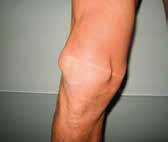

Handelt es sich jedoch um schwere langstreckige Verletzungen, die teilweise neben den Bandrekonstruktionen auch knöcherne Stabilisierungen mit Platten-/Schraubensystemen erforderlich machen, scheint der Gipsabdruck immer noch das Mittel der Wahl zu sein. Dabei muss vom versierten Techniker die Längenbestimmung der Schalen am Ober- und Unterschenkel festgelegt werden, um z. B. kritische Zonen bei Plattenstabilisationen und Kraftspitzen bei einer wiederaufgenommenen sportlichen Aktivität mit großen Hebeln zu vermeiden. Dies ist gerade im alpinen Skilauf ein wichtiger Faktor (Abb. 7a u. b).